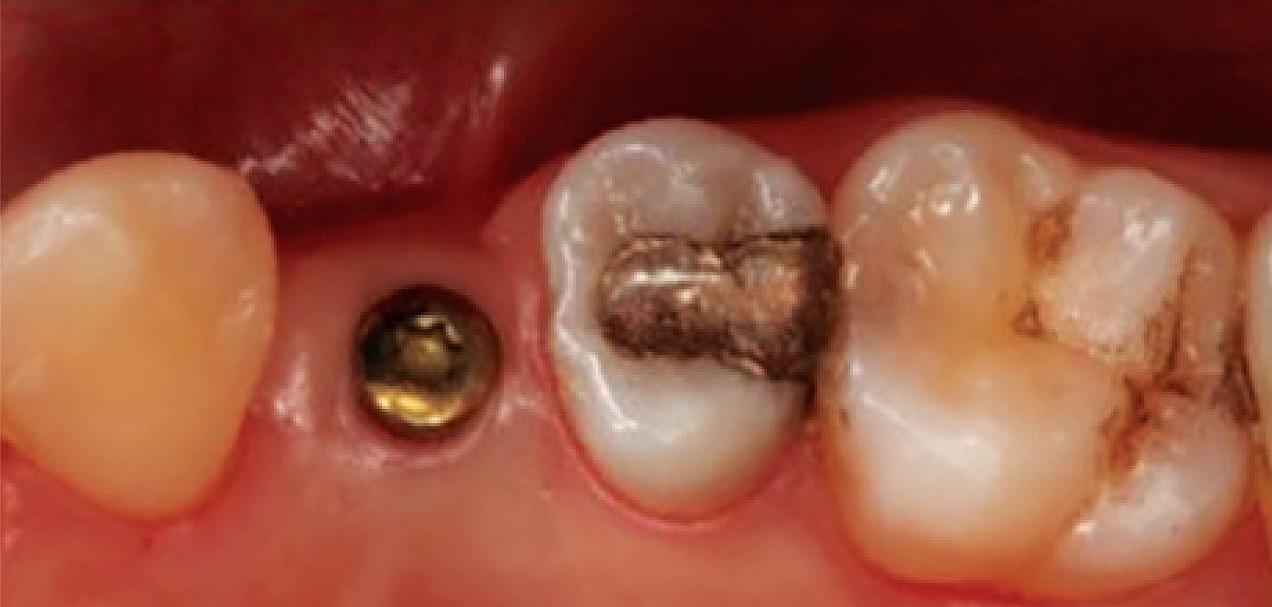

Figure 1: Radiographic Image of implants do not demonstrate bone loss due to the bisecting angle of the radiograph taken.

Figure 2: Radiographic image in a paralleling technique of implants dem onstrate moderate peri-implantitis with bone loss that will necessitate treatment.